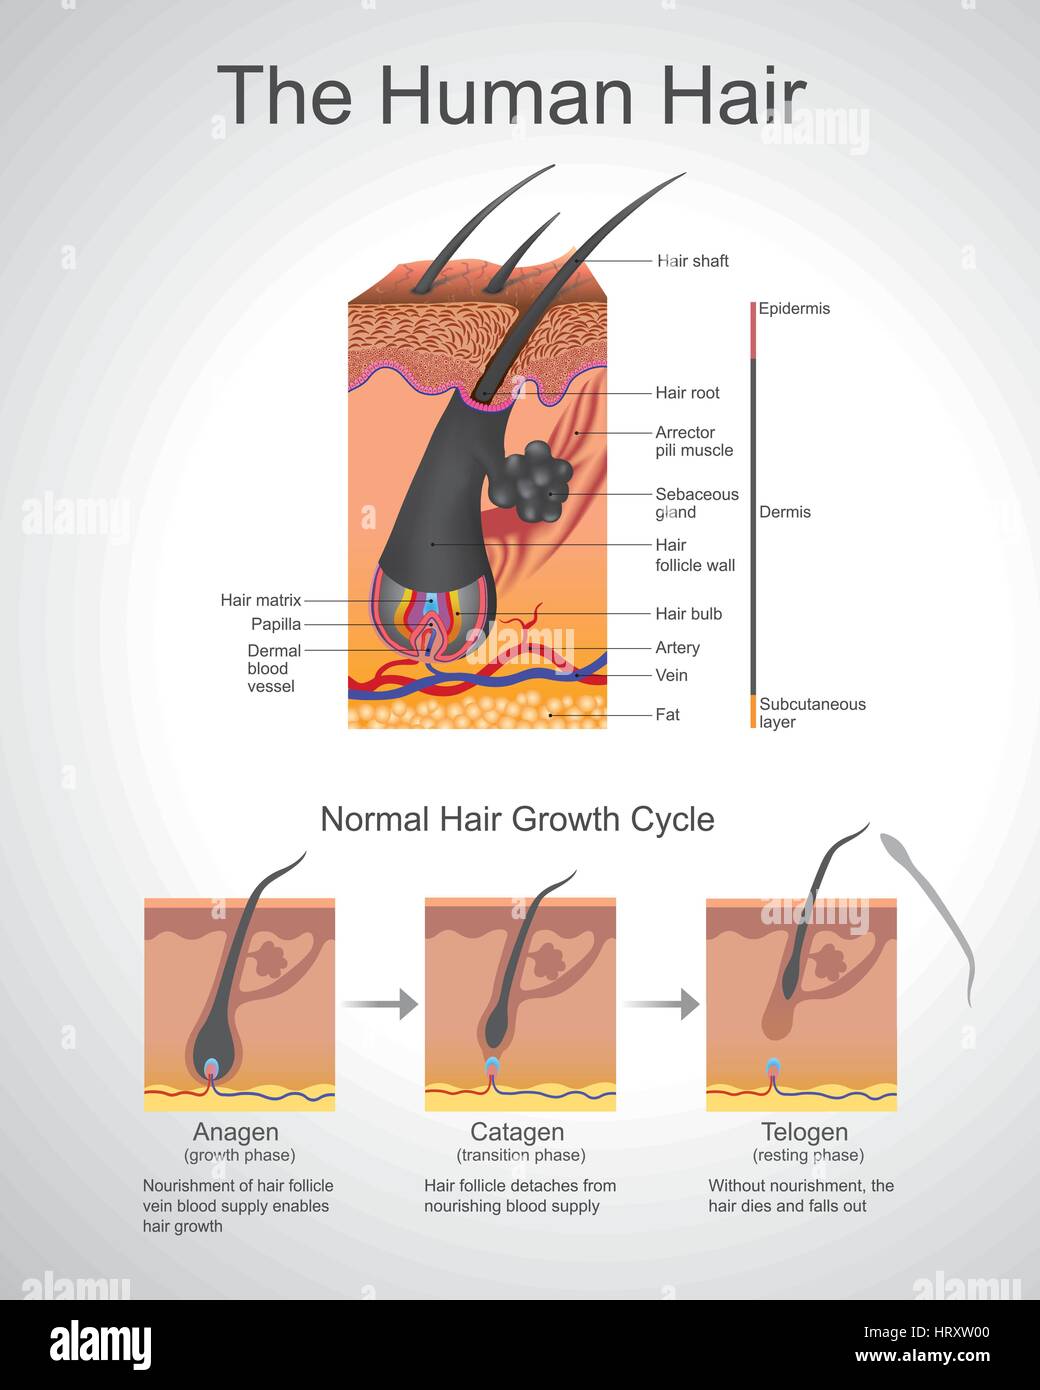

Capelli segue un determinato ciclo di crescita con tre distinti e fasi contemporanee anagen e catagen e telogen fasi Illustrazione Vettorialehttps://www.alamy.it/image-license-details/?v=1https://www.alamy.it/capelli-segue-un-determinato-ciclo-di-crescita-con-tre-distinti-e-fasi-contemporanee-anagen-e-catagen-e-telogen-fasi-image211491825.html

Capelli segue un determinato ciclo di crescita con tre distinti e fasi contemporanee anagen e catagen e telogen fasi Illustrazione Vettorialehttps://www.alamy.it/image-license-details/?v=1https://www.alamy.it/capelli-segue-un-determinato-ciclo-di-crescita-con-tre-distinti-e-fasi-contemporanee-anagen-e-catagen-e-telogen-fasi-image211491825.htmlRFP827YD–Capelli segue un determinato ciclo di crescita con tre distinti e fasi contemporanee anagen e catagen e telogen fasi

Capelli segue un determinato ciclo di crescita con tre distinti e fasi contemporanee anagen e catagen e telogen fasi. Ogni fase ha specifici characteri Illustrazione Vettorialehttps://www.alamy.it/image-license-details/?v=1https://www.alamy.it/foto-immagine-capelli-segue-un-determinato-ciclo-di-crescita-con-tre-distinti-e-fasi-contemporanee-anagen-e-catagen-e-telogen-fasi-ogni-fase-ha-specifici-characteri-135200016.html

Capelli segue un determinato ciclo di crescita con tre distinti e fasi contemporanee anagen e catagen e telogen fasi. Ogni fase ha specifici characteri Illustrazione Vettorialehttps://www.alamy.it/image-license-details/?v=1https://www.alamy.it/foto-immagine-capelli-segue-un-determinato-ciclo-di-crescita-con-tre-distinti-e-fasi-contemporanee-anagen-e-catagen-e-telogen-fasi-ogni-fase-ha-specifici-characteri-135200016.htmlRFHRXW00–Capelli segue un determinato ciclo di crescita con tre distinti e fasi contemporanee anagen e catagen e telogen fasi. Ogni fase ha specifici characteri